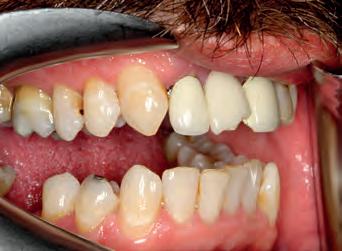

TOP ROW: Before lower occlusal, Before retracted in occlusion 2ND ROW: Before retracted left in occlusion, Before retracted left open 3RD ROW: Before retracted open, Before retracted right in occlusion 4TH ROW: Before retracted right open, Before upper occlusal